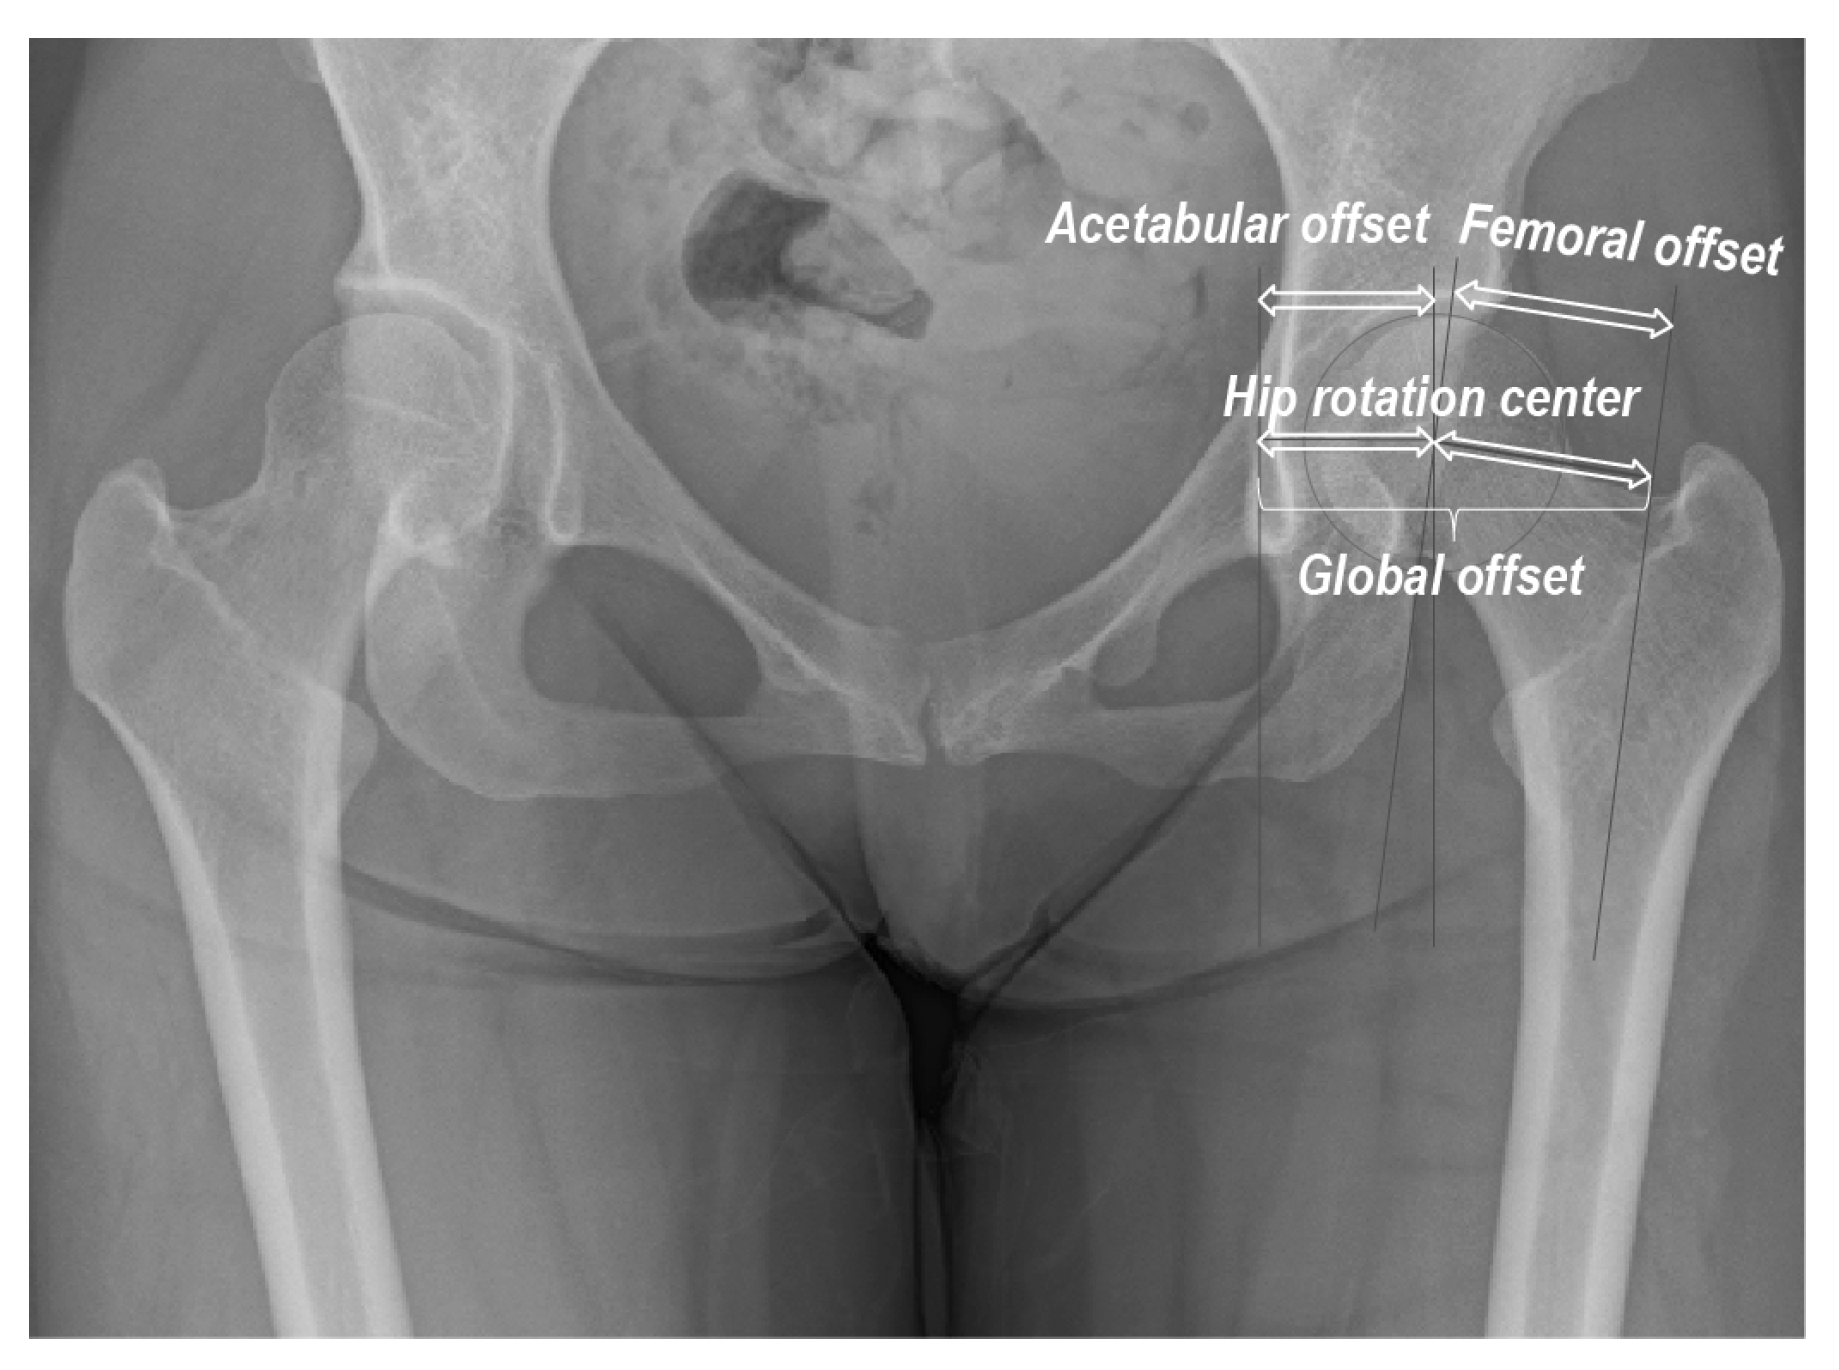

Radiographs were obtained using Siebenrock’s standardized technique [20]. We evaluated the CE angle, FO (length of the perpendicular line between the HRC and femoral axis), acetabular offset (AO; length of the perpendicular line between the HRC and the vertical line across the inferior edge of the teardrop center), and global offset (GO; sum of the AO and FO; Figure 1) [21]. All digital measurements and calculations were performed using the Centricity™ Web-J 3.0 HD software (GE Healthcare Japan, Tokyo, Japan). Measurements were performed twice, with a 3-month interval, by the two first authors (T.S. and H.I.). The intra- and inter-class correlation coefficients were excellent (0.962 and 0.894, respectively; p < 0.001 for both).

Figure 1. Radiographic hip morphometric parameters analyzed in this study.